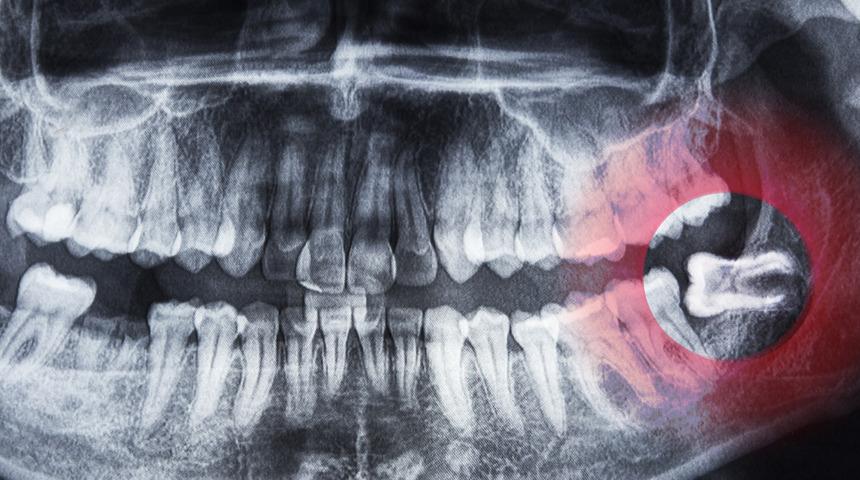

Hastaneden yapılan açıklamada görüşlerine yer verilen Aktaş, çene kemiğinde tamamen ya da kısmen kalan, genellikle azı dişlerinde, özellikle 20'lik dişlerde sıkça karşılaşılan gömülü dişlerin ağrı, şişlik ve iltihap gibi rahatsızlıklara yol açabileceğini belirtti.

20'LİK DİŞLER GENELLİKLE GÖMÜLÜ KALIYOR

Aktaş, özellikle 20'lik dişlerin genellikle gömülü kaldığını, bu durumun daha fazla ağrıya ve çeşitli enfeksiyonlara yol açabileceğini dile getirerek, "Gömülü dişler genellikle panoramik röntgen gibi görüntüleme yöntemleriyle tespit ediliyor. Gömülü dişlerin erken dönemde fark edilmesi, ileride karşılaşılabilecek komplikasyonların önüne geçilmesini sağlar. Bu nedenle düzenli diş hekimi kontrolleri büyük önem taşır." ifadelerini kullandı.